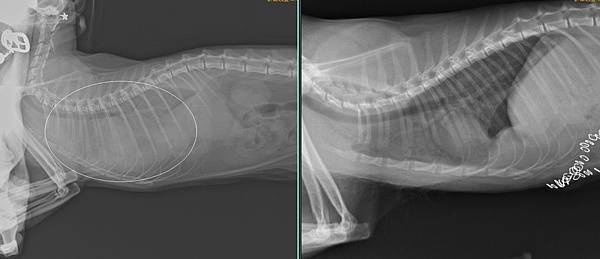

Cleo是一位九個月大的小朋友,媽媽遠從苗栗來找小譚醫師,說Cleo被檢查到橫膈膜破裂,肝臟掉到胸腔扭轉,肝指數已經高到驗血儀器檢查不出來了。

這已經屬於非常嚴重的情況,醫療團隊感快安排手術,手術發現,Cleo已經出血很嚴重血腹,肝臟也整個在胸腔打結,所幸在通力協助下,把破洞的橫膈膜仔細修補,肝臟也解開打結放回原本的位置。Cleo很爭氣的恢復很好,今天回來拆線也都一切正常。